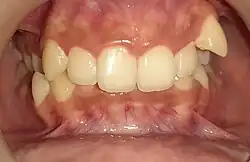

Overbite is the extent of vertical (superior-inferior) overlap of the maxillary central incisors over the mandibular central incisors,[1] measured relative to the incisal ridges.[2]

The term overbite does not refer to a specific condition, nor is it a form of malocclusion. Rather an absent or excess overbite would be a malocclusion. Normal overbite is not measured in exact terms, but as a proportion (approximately 30–50% of the height of the mandibular incisors) and is commonly expressed as a percentage.